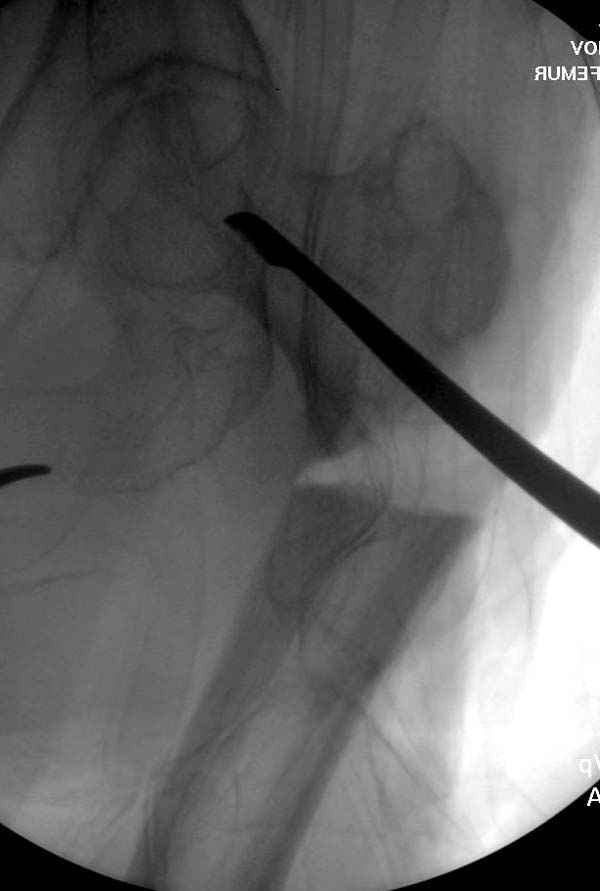

Не стали усложнять интрамедуллярным вариантом коррекции, легче контролировать коррекцию пластиной, поэтому сделали операцию 95 градусной Blade Plate, разогнув до 110 градусов.

Страйкер предоставил отличный инструмент - крючок для удаления длинного гвоздя. Считаем, что врачебная ошибка по установке привела к несостоятельности импланта и к ятрогенному осложнению.